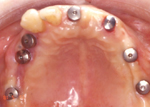

典型的なインプラント治療の症例10

50代 男性

治療前

物が噛めないということで来院された方です。

虫歯と歯周病が進み、上顎下顎ともに全体的な治療が必要です。骨の状態や患者様のご希望から、上顎はインプラント義歯として4本のインプラントを、下顎には固定式の4本のインプラントを埋入することになりました。

治療後

上顎

下顎

虫歯の治療、歯周病の治療をし、全ての歯の治療がおわりました。

上顎はインプラント義歯、下顎は固定式の冠を装着したインプラントです。